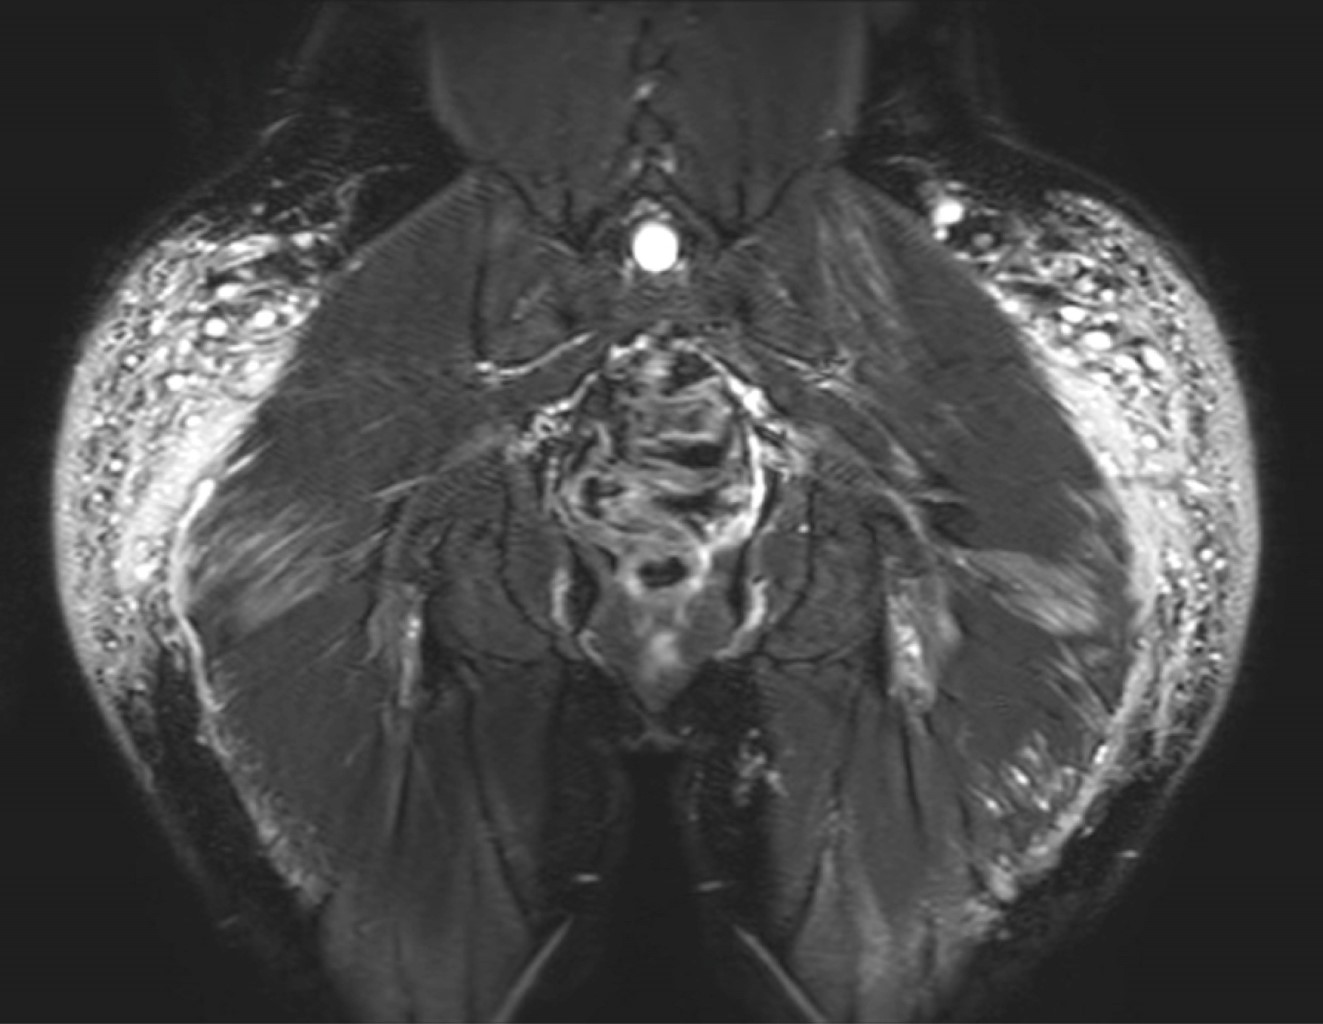

Paciente de 30 años con antecedentes de aplicación de modelantes en las regiones glúteas hace 10 años. Desde hace tres años presenta dolor en ambas piernas, con zonas induradas y cambios de coloración. Se le realizó resonancia magnética de las regiones glúteas y piernas identificando imágenes globulares y lineales irregulares de comportamiento isointenso en el T1, hiperintenso en el T2, hiperintenso en las secuencias de saturación grasa (Fat-Sat) y en STIR (Short Inversion Time Inversion Recovery) con compromiso de los tejidos blandos superficiales y de los planos musculares que afectan a los glúteos mayor y medio (Figuras 1 y 2).

La resonancia magnética es el método de diagnóstico de elección, permite la localización del material modelante, su distribución, extensión y profundidad a los tejidos adyacentes. La mayoría de estas sustancias están compuestas por agua, con comportamiento hipointenso en T1, hiperintenso en T2 y T2 con supresión grasa (STIR, Fat-Sat, SPAIR) y por su alto peso molecular, son hiperintensos en secuencias T2 con supresión de grasa y agua (silicon-only o FSE T2 IR), el tejido inflamado realza con el contraste (gadolinio). Estas características permite identificarlas, pero no ayuda a determinar el material utilizado.3 Los patrones de distribución son: globulares, lineales o pseudonodulares. Pueden existir adenomegalias. Las aplicaciones más frecuentes se dan en las regiones glúteas con repercusión hacia los músculos glúteo mayor y medio.1

Figura 1

Figura 2